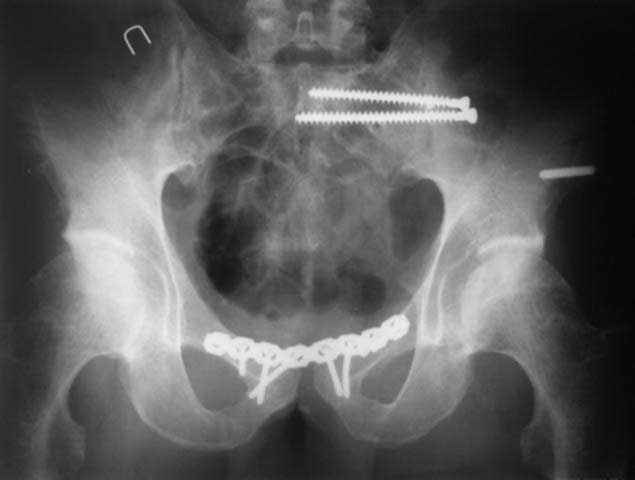

Дорогой Андрей. Мы имеем дело с комбинированной (ротационно и вертикально) нестабильностью таза со смещением правого гнемипелвиса. При таких переломах, фиксация только переднего полукольца вне зависимости от метода фиксации, как уже было сказано Djoldas Kuldjanov, M.D., не может создать адекватной фиксации. И перелом пластины был вполне ожидаемым после активизации пациента. Смещение сохраняется, и по-видимому не 2 см., а все 4, если не более. Разница всего (+2 см) по конечностям как вы указываете, скорее скомпенсировано позвоночником и протезом. Дополнительные снимки или КТ исследование помогли бы уточнить степень смещения с точностью до мм., выявить перелом поперечного отростка пятого поясничного позвонка, или помимо разрыва правого крестцово-подвздошного сочленения выявить перелом боковой массы крестца справа и т.д. При возможности, конечно, все это желательно сделать. Но мало что изменится с практической точки зрения, т.к. задача - это низведение репозиция и надежная фиксация правого гемипелвиса. Учитывая плачевный опыт стержневого аппарата, давность травмы совершенно очевидно, что поставленная задача достижима при открытой репозиции и одномоментной фиксации переднего полукольца с артродезированием правого крестцово-подвздошного сустава. Операция выполняется в положении больного на здоровом боку или полубоку из расширенного трансоссального подвздошно-пахового доступа с переходом на лонное сочленение доступом по Pfannenstiel. Указанный доступ обеспечивает подход к крестцово-подвздошному сочленению как спереди так и сзади. После артродезирования выполняется синтез лонного сочленения. Клинический пример

Пациентка С.26 лет. Травма за 6 месяцев до поступления

Укорочение правой нижней конечности до 10см

23.09.2003. Одновременный остеосинтез переднего и заднего тазовых полуколец

Результат через 10 дней

и 8месяцев после операции